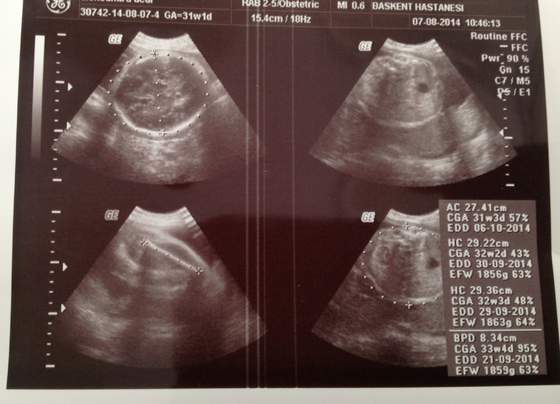

Dziewczyny, dzisiaj 31w1d, bylam na usg, lekarka powiedziala, ze Maly wielkosciowo wyprzedza 10dni...

Zmrozilo mnie, wymarzylam sobie 2900g, tak zeby podczas porodu naturalnego uniknac pekniecia i naciecia, na ostatnim usg waga byla 900g teraz ponad 2 razy tyle.. Rzeczywiscie jest wielki? My oboje jestesmy niscy, w rodzinie meza same karyple, ale moj tata 186cm, i wlasnie podczas porodu wazyl ok 5kg